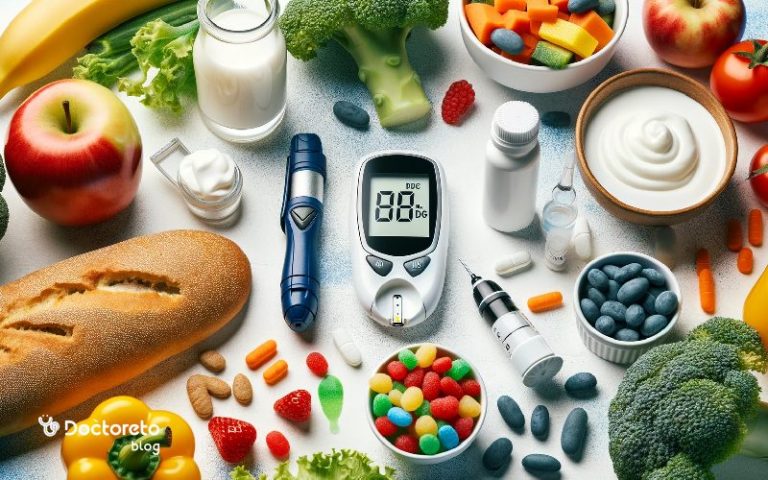

کسانی که دیابت دارند چه غذاهایی بخورند؟ مهمترین اقدام...

یکی از سوالاتی که بسیاری از افراد بعد از...